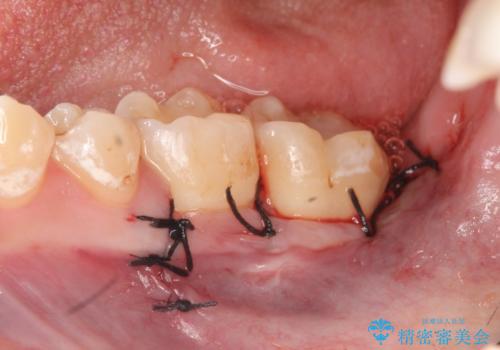

左下7の虫歯は深く、また歯冠高径も低かったため、歯冠長延長術を行いました。

術後歯肉の回復を待ち、左下6はセラミックインレー、左下7はオールセラミッククラウンにて補綴しました。

歯冠長延長術とは歯肉弁根尖側移動術とも言い、歯の高さが低くクラウン(被せ物)による治療が難しい場合に、歯茎を歯根方向に下げることで歯の高さを確保する手術です。歯の高さが十分にあることで、外れにくいしっかりとしたクラウンを被せることができます。

虫歯が進み歯茎より深くなってしまうと、虫歯を取り残してしまうリスク、樹脂の硬化の妨げ、補綴物の不適合、歯肉炎・歯周病のリスクの増大等様々な弊害が起こり得ます。

そのため当院では歯周外科手術(歯茎を下げる手術)や歯の挺出による、虫歯が歯茎より深いという問題の解決を推奨しております。